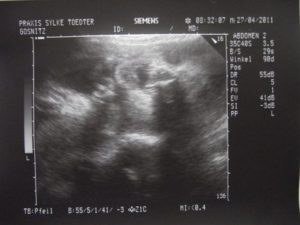

Более того, всем беременным женщинам необходимо регулярно проходить данное исследование, и делается в следующих целях: наблюдение за развитием плода и состоянием организма женщины.

Одним из элементов ультразвукового исследования при беременности или при ее планировании является изучение желтого тела.

Наблюдение за этим процессом осуществляется при помощи такого простого метода как ультразвуковое исследование. Обычного это необходимо на этапе планирования и в первые недели наступившей беременности, а также при лечении бесплодия или прочих патологиях яичников.